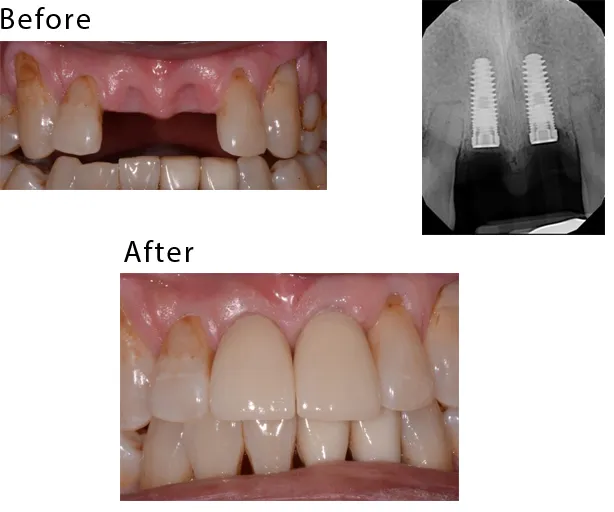

The case studies below illustrate a variety of procedures and results achieved for patients of the California Dental Specialty Group.